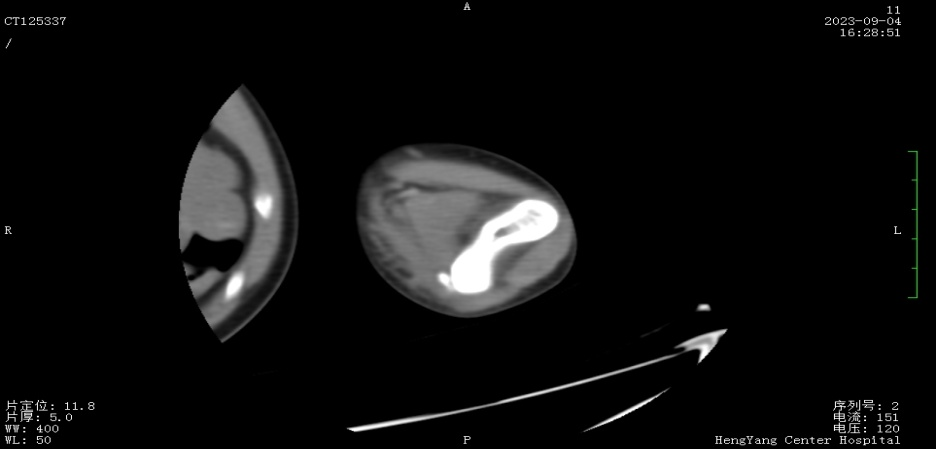

接診后,醫(yī)師發(fā)現小莫同學的左肘關節(jié)自然狀態(tài)下僅能伸展至約115°,并伴有習慣性屈肘。經與骨科醫(yī)生溝通并閱片后,考慮骨化肌炎,針對這種情況,一般采取手法松解關節(jié)和關節(jié)功能鍛煉相結合的治療方案。但此方案常用于成人患者的關節(jié)粘連傳統(tǒng)松解術和關節(jié)松動訓練,對于兒童來說刺激強度太大,且因兒童骨骼及關節(jié)較成人脆弱,無法保證治療的連續(xù)性及安全性,若一味采取輕柔手法,不僅治療時間長、見效慢,還可能加重后續(xù)治療難度

圖片1.png

面對這一難題,經科室討論后,最終確定了以針刺運動療法為主的治療方案。正式治療時,康復醫(yī)師先用輕手法松解患處關節(jié)10分鐘后,使小莫同學手臂自然放松,后選取相應穴位后以寸針刺入,經捻轉得氣后留針,并帶針運動5至10分鐘,出針后持續(xù)牽伸關節(jié)。

圖片2.png

首次治療結束后,小莫同學的左肘關節(jié)即可伸展至145°。9月19日,小莫同學已結束第一階段共14次治療,他的左肘關節(jié)就可以自然伸展至170°,可滿足上肢基本功能需求。